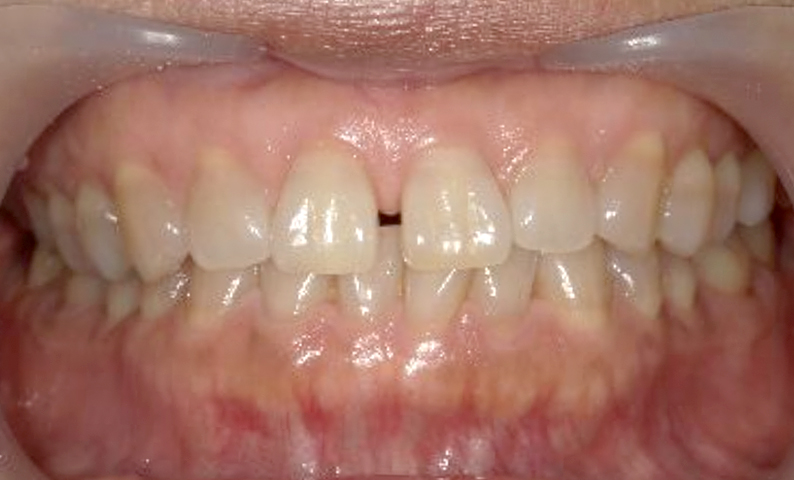

症例:上顎だけの部分矯正

治療期間:7ヶ月金額:24万円+税10代女性すきっ歯上の前歯だけ歯の形態修正